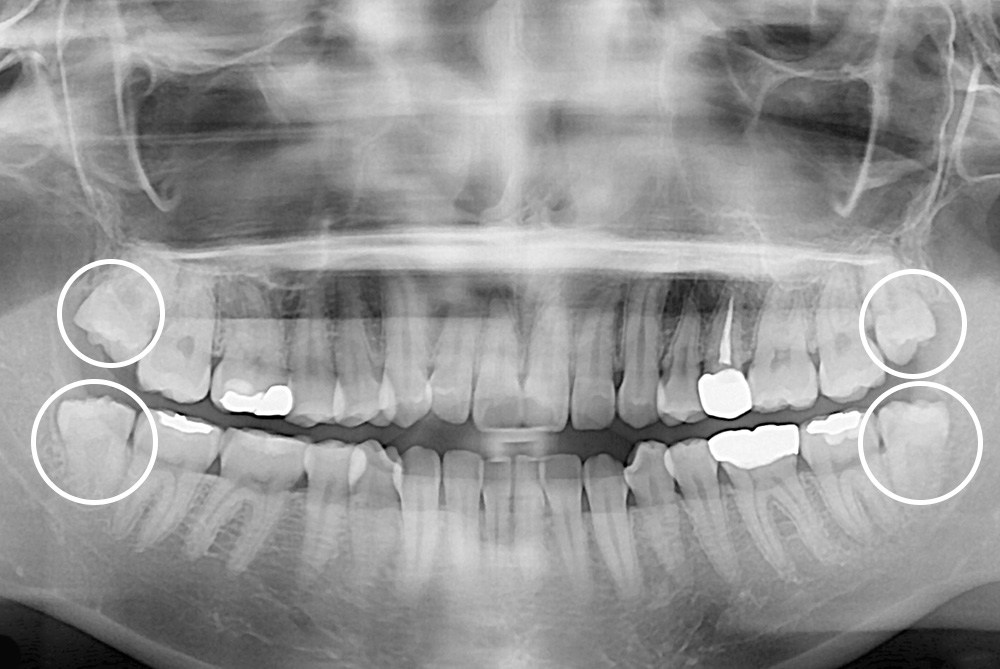

[사랑니] 매복 사랑니 발치

치료전 : 2018-11-16